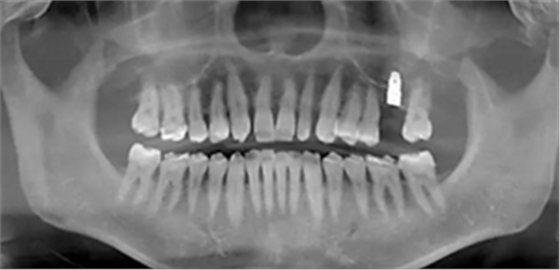

患者:男,37歲。左上后牙確實(shí)多年。既往體健,否認(rèn)麻醉和牙槽外科禁忌。

術(shù)前口內(nèi)照

術(shù)前CBCT檢查

骨高度不足,內(nèi)提升的適應(yīng)癥??梢姼]膜致密,厚度均勻。骨高度不足,骨寬度尚可。